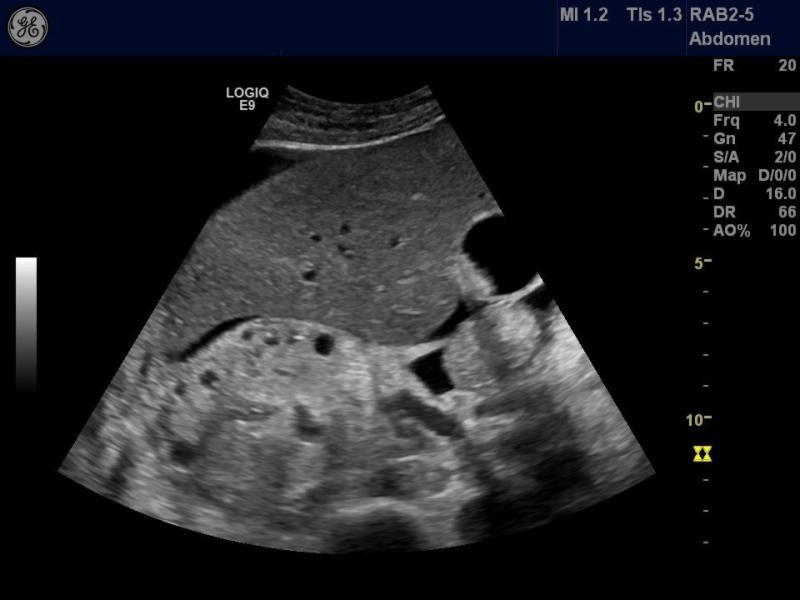

청아병원에 새롭게 도입된 LOGIQ E9는 GE 헬스케어에서 생산하는 최고사양의 최신 초음파 장비로서 초음파 검사 환자의 대기시간 단축과 장비의 고급화를 꽤하여 정확한 진단이 가능하게 되었습니다.

이번에 도입된 LOGIQ E9는 실시간 이미지와 고해상도의 선명한 영상, 3차원 입체컬러 영상을 함께 표현해 진단의 정확성을 높였으며, 특히 복부(심장, 맹장 등), 혈관, 유방검사 등 인체 각 질환의 정확한 진단에 많은 장점을 가지고 있습니다.